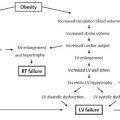

Simon et al1 published a useful classification of gynecomastia, with grades 1, 2A, 2B, and 3 corresponding to increasing deformity ( Table 23.1 ). The majority of postbariatric patients are placed in grade 3, with marked skin redundancy with or without breast enlargement. In defining the role of suction-assisted and ultrasonic liposuction, Rohrich et al2 developed four grades; the two severe grades, III and IV, are pertinent here ( Table 23.2 ). Grade III exhibits grade I nipple ptosis, whereas grade IV exhibits grade II or III nipple ptosis. The authors advocate ultrasound-assisted liposuction (UAL) with or without staged excision. More than 85% of patients in their series did not require a second open procedure. Only 11% of patients in their series, however, presented with grade IV severity. Song et al3 present a post-bariatric rating scale for breast deformities, but it includes only female patients.